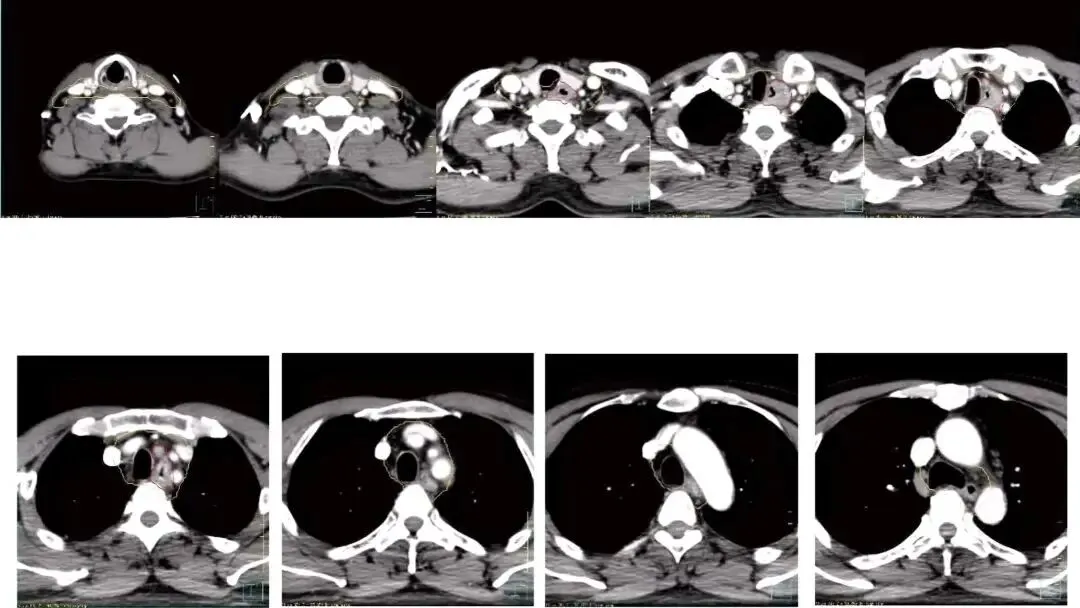

累及野照射:上下外放2—3cm

IFI(累及野照射):现代精准放疗理念,仅照射影像学上明确的肿瘤区域和转移淋巴结。

最新证据:2023年研究表明,IFI与ENI相比,总生存率相似,且区域失败率未见显著增加,但毒性(如骨髓抑制)更低。因此,IFI可能成为更优选择

六、医肿颈段食管靶区勾画